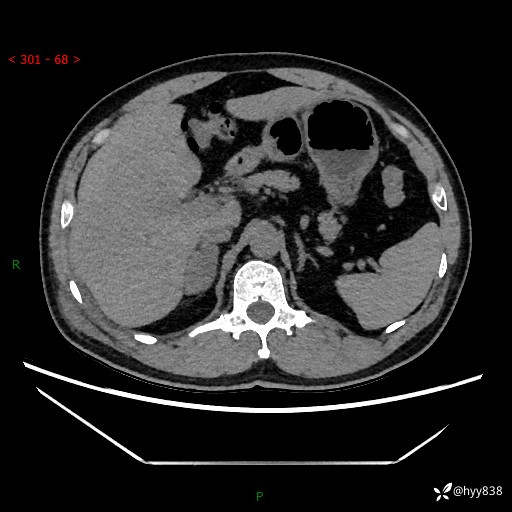

现病史:患者9月4日摔伤在深圳市宝安区中心医院行CT检查提示右侧肾上腺区结节(38*27mm),复查B超提示右侧肾上腺区可见一61*24mm异常低回声团,建议进一步检查。进一步完善增强CT后提示:右侧肾上腺区肿块及周围渗出改变,大致同前,考虑肾上腺腺瘤,不除外瘤内出血可能,否认阵发性头晕、头痛、出汗、乏力等不适,门诊以“ 右侧肾上腺肿瘤”收入住院。 起病来,患者精神、食欲、睡眠可,大便通畅,小便如上述,体力体重无明显改变。

增强(动脉期+静脉期)

单侧肾上腺病变,鉴别诊断有哪些